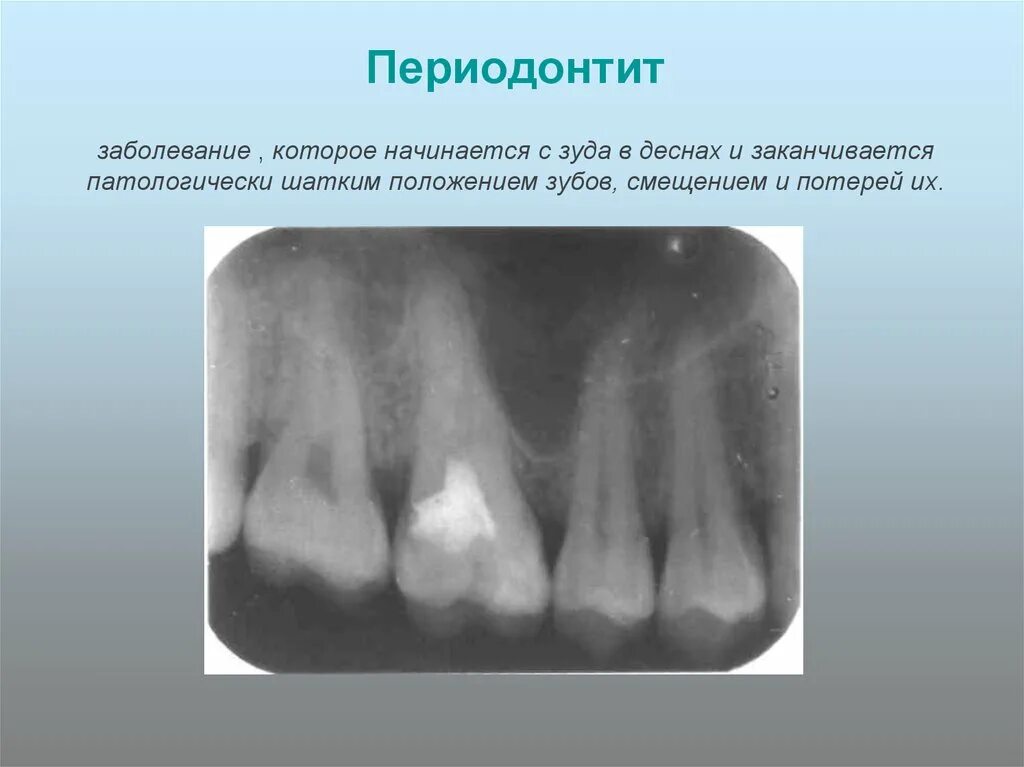

Как понять снимок зуба